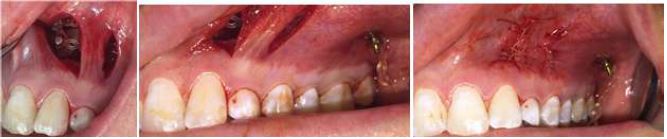

Clinical Procedure

After receiving authorization of the treatment plan from the patient's parents and signed informed consent, a modified palatal button with double tubes welded to the upper first molar bands was installed. In addition, a steel arm welded to the 26 band was included in order to replace the miniscrew of the technique described by Chang (Figure 8).

The surgical intervention was performed under local anesthesia. It began with two vertical incisions, the first in the buccal gingiva between 22 and 63, and the second in the buccal gingiva at the level of 24 to make the subperiosteal tunnel by dissecting the soft tissue. An osteotomy was performed to discover the crown of 23 and a conductive osteotomy towards the distal. The button was adhered to the crown of 23 and an elastic chain was installed from the buccal button of 23 through the subperiosteal tunnel to the post welded to the band of 26. Thus, distalization force of 23 could be applied, and improve its eruption pathway (Figure 8).

On the other hand, tooth 13 underwent a closed surgical window that began with an incision at the height of the crown. An osteotomy was performed in its cervicoincisial length, adhesion of the button to the crown, and installation of an elastic chain. A 0.017" x 0.025" TMA cantilever was adapted to the auxiliary band tube of tooth 16, to which a chain previously installed in the button of 13 was adapted, initially with a distalization vector force. Both approaches were completed with hemostasis and suture.

Surgical Procedure with VISTA Technique, Case 2

FIGURE 8

Surgical procedure showing VISTA technique, incisions, position of the button with direct cementation, second generation chain, through the subperiosteal tunnel, and the modified tooth-supported palatal button, cemented through bands to teeth 16 and 26. Source: the authors with permission from the patient.